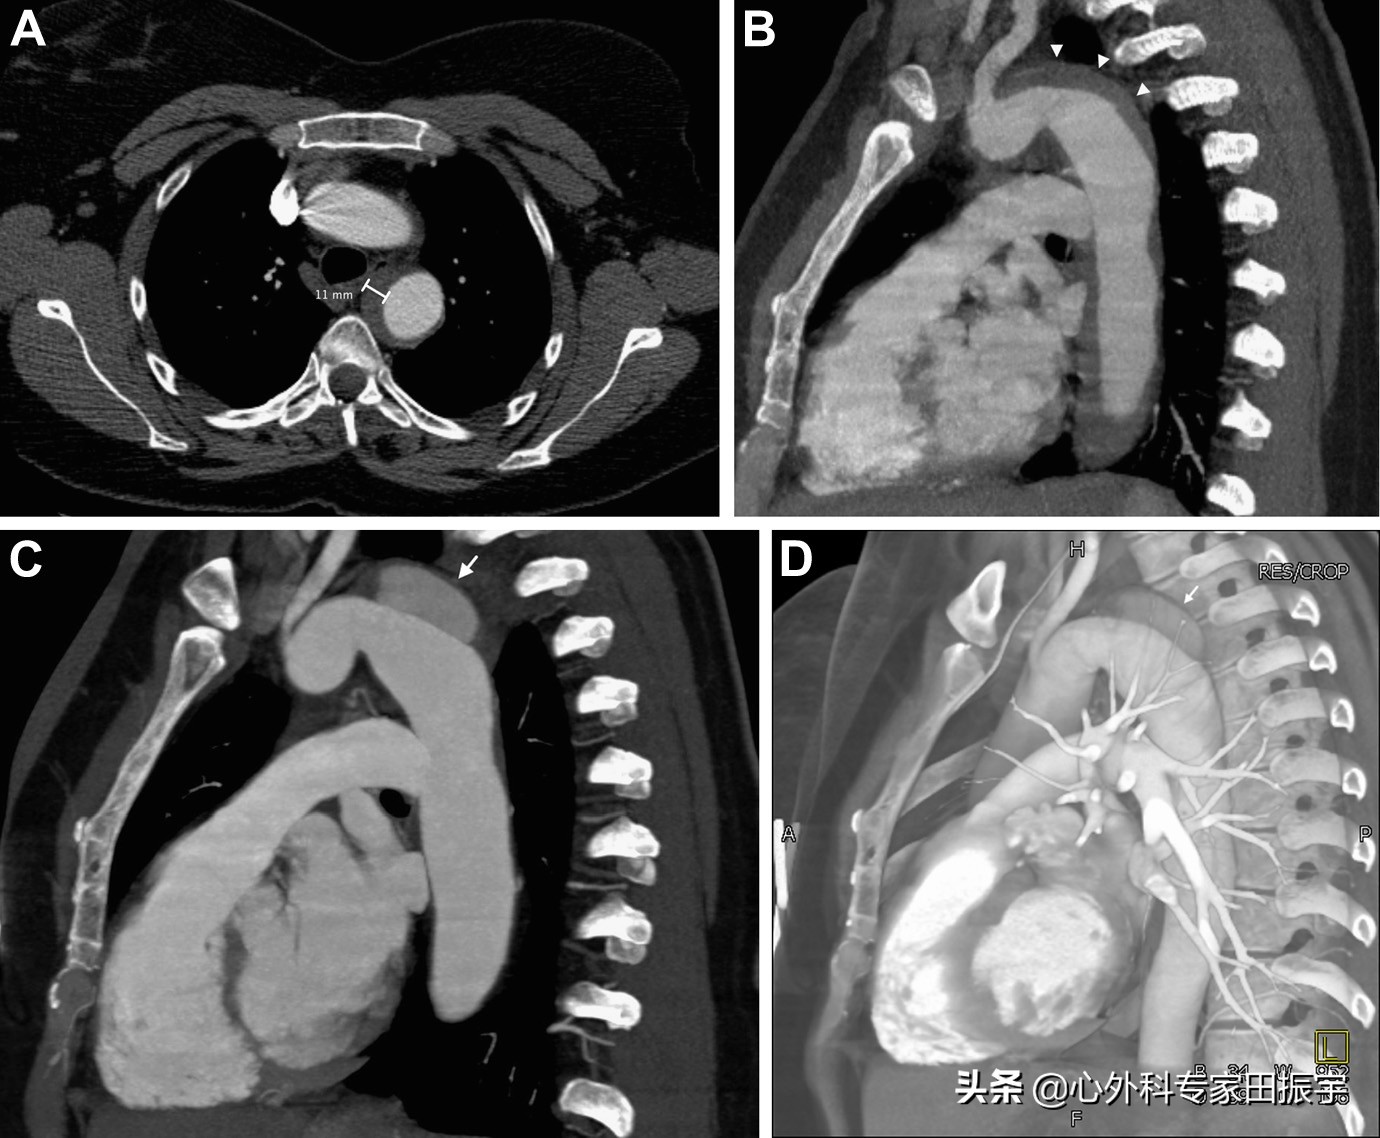

主动脉壁间血肿

图4 一名43岁妇女出现急性背痛和高血压危象。增强CT的轴向(A)和矢状多平面重建(B)CT 图像显示 B 型壁间血肿,血肿厚度为 11 mm(箭头)。3 个月后随访增强CT多平面重建图像(C)和三维体积重建图像(D)显示主主动脉弓远心端发展成假性动脉瘤(箭头)。

图5 在一名45岁女性胸痛,可疑主动脉夹层,胸部平扫轴向CT图像显示,一种A型主动脉壁间血肿(箭头)厚度为6毫米。